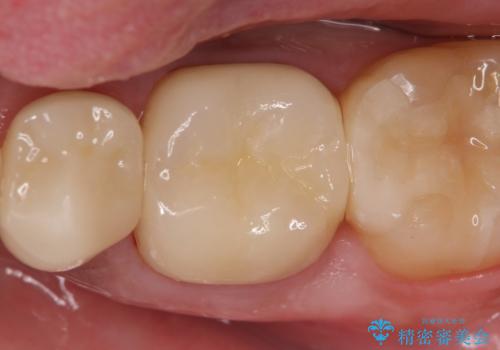

前歯は被せものをやり替えるだけでよいかのように見えますが、見えない部分で外部吸収が進行し、歯が虫食い状に吸収されてしまっています。残念ながら、外部吸収が深い位置で進行すると、吸収性の組織を取り除く意義も兼ねて、抜歯が第1選択となってしまいます。

右上の前歯は部分矯正により歯を引っ張り出すことでなんとか保存しています。

仮歯・部分矯正・抜歯など、山口先生にて処置をされ、最終的な完成のみ引き継がせていただきました。今後はマウスピースの装着・スーパーフロスによる清掃などを継続していっていただく必要があります。